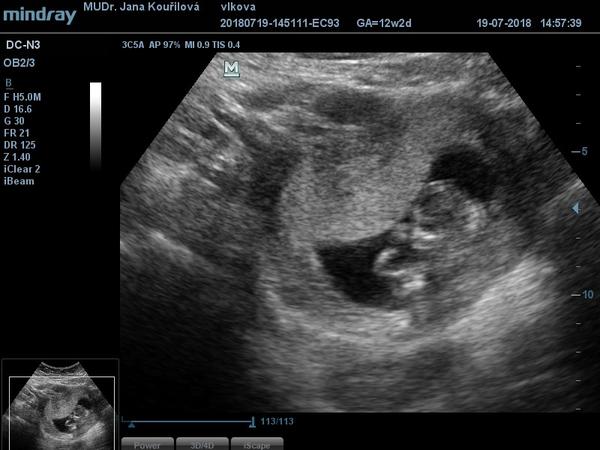

@hribek čárka je krásná!!!! Ty se cítíš jak? Já po tom druhém pokusu jsem se od začátku cítila úplně jinak, že jakoby jsem vnitřně cítila, že to bude ok. ve čt jsem byla na kontrole, 12+2, mimčo si tam hovělo s opřenýma nožičkama, pak paleček v puse...krása. Ve středu jdu na screening, tak snad bude taky vše ok. Pak začnu přemýšlet, kdy to řeknu v práci

@crazy_girl3 krasny fotecky

@luciebx děkuju 🙂 už to vypadá jako miminko ❤